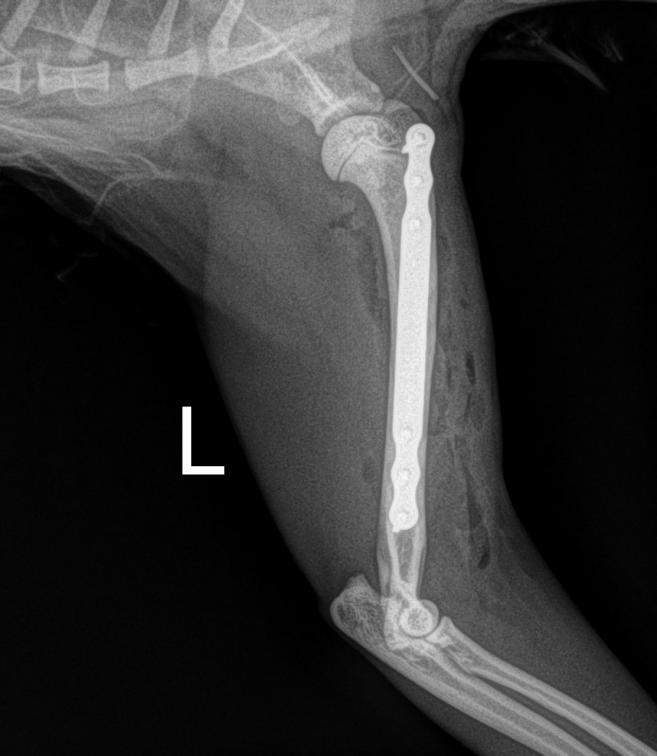

Day 1: He had to fix a humerus spiral fracture (left) with a LeiLOX bridge plate. Furthermore, he diagnosed a femur transverse fracture. Dr. Sonntag then used a 7-hole LeiLOX plate to repair this fracture, and do several emergency soft tissue surgeries.

(Surgery time: 1:15 hours)

“Especially remarkable are the short surgery times.

On this aspect, the LeiLOX System has once again proven one of its many important capabilities.

With conventional plates, this would not have been possible. LeiLOX was the reason why I could repair everything in ONLY two surgeries.”